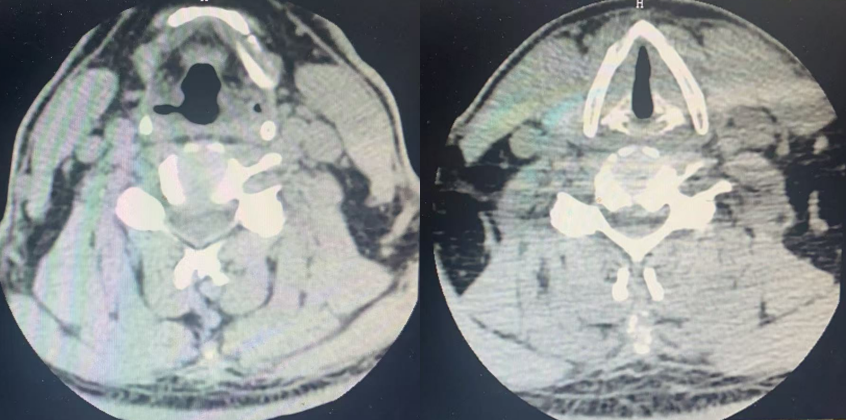

CT

颈生理曲度变直,退行性改变。

2-3、颈3-4、颈5-6及颈6-7椎间盘不同程度突出。

4-5椎间盘轻度右后突出;

项韧带部分骨化;

双肺下叶背侧轻度间质改变;

冠脉钙化积分:冠状动脉中度钙化。